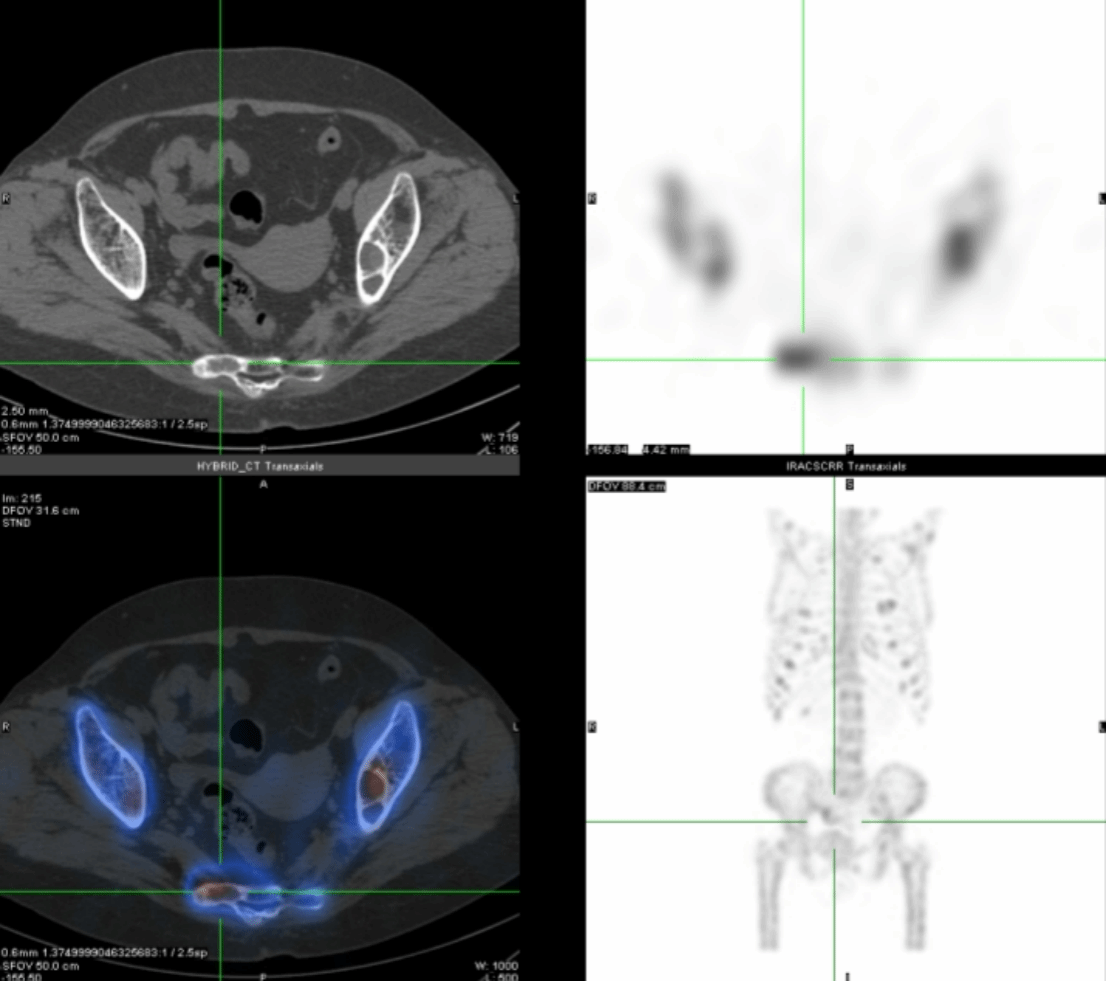

进一步的SPECT/CT断层融合显像(图2-4)显示:肋骨、肩胛骨、骶骨等灶性异常显像剂浓聚处伴骨质膨胀性骨质破坏。

通过全身显像,可以判断这些异常并非骨转移瘤所引起,而是一种代谢性骨病,结合SPECT/CT所示多发溶骨性骨质膨胀性破坏,考虑为甲状旁腺功能亢进所致代谢性骨病伴棕色瘤。为了进一步验证,段阿姨进行了血清电解质和甲状旁腺激素的测定,结果显示她的血清钙(3.14mmol/L)和甲状旁腺激素(1548pg/ml)水平明显增高,从而证实了甲状旁腺功能亢进症的诊断。段阿姨无慢性肾脏疾病、骨软化症、肠吸收不良综合征、维生素D缺乏等疾病的病史,因此诊断为原发性甲状旁腺功能亢进症。原发性甲状旁腺功能亢进症首选治疗方法为手术[1],而手术的成功主要取决于术前对功能亢进的甲状旁腺病变的精确定位,甲状旁腺显像则对识别功能亢进的甲状旁腺病变具有非常重要的意义[2]。